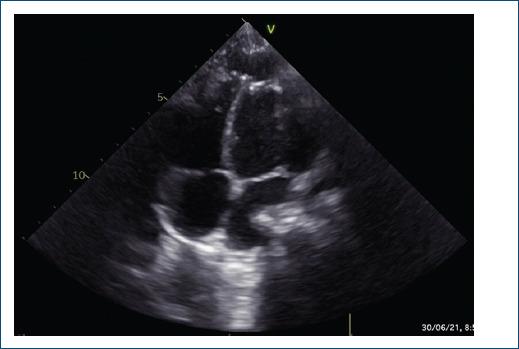

Aneurysms and diverticula of the left ventricle are rare entities in childhood, with a prevalence of less than 0.1%. Described since 1886, as a severe and potentially fatal disease if not corrected, mainly due to the presence of associated anomalies and the risk of rupture.

Endovascular management of the left ventricular diverticulum, diagnosed prenatally in the patient presented, was successful after initial failure with surgical management.

左心室动脉瘤和憩室在儿童时期较为罕见,患病率低于0.1%。自1886年以来就有相关描述,若不纠正,这是一种严重且可能致命的疾病,主要是由于存在相关异常以及破裂风险。

本文所呈现患者产前诊断出的左心室憩室,在手术治疗初次失败后,血管内治疗取得成功。